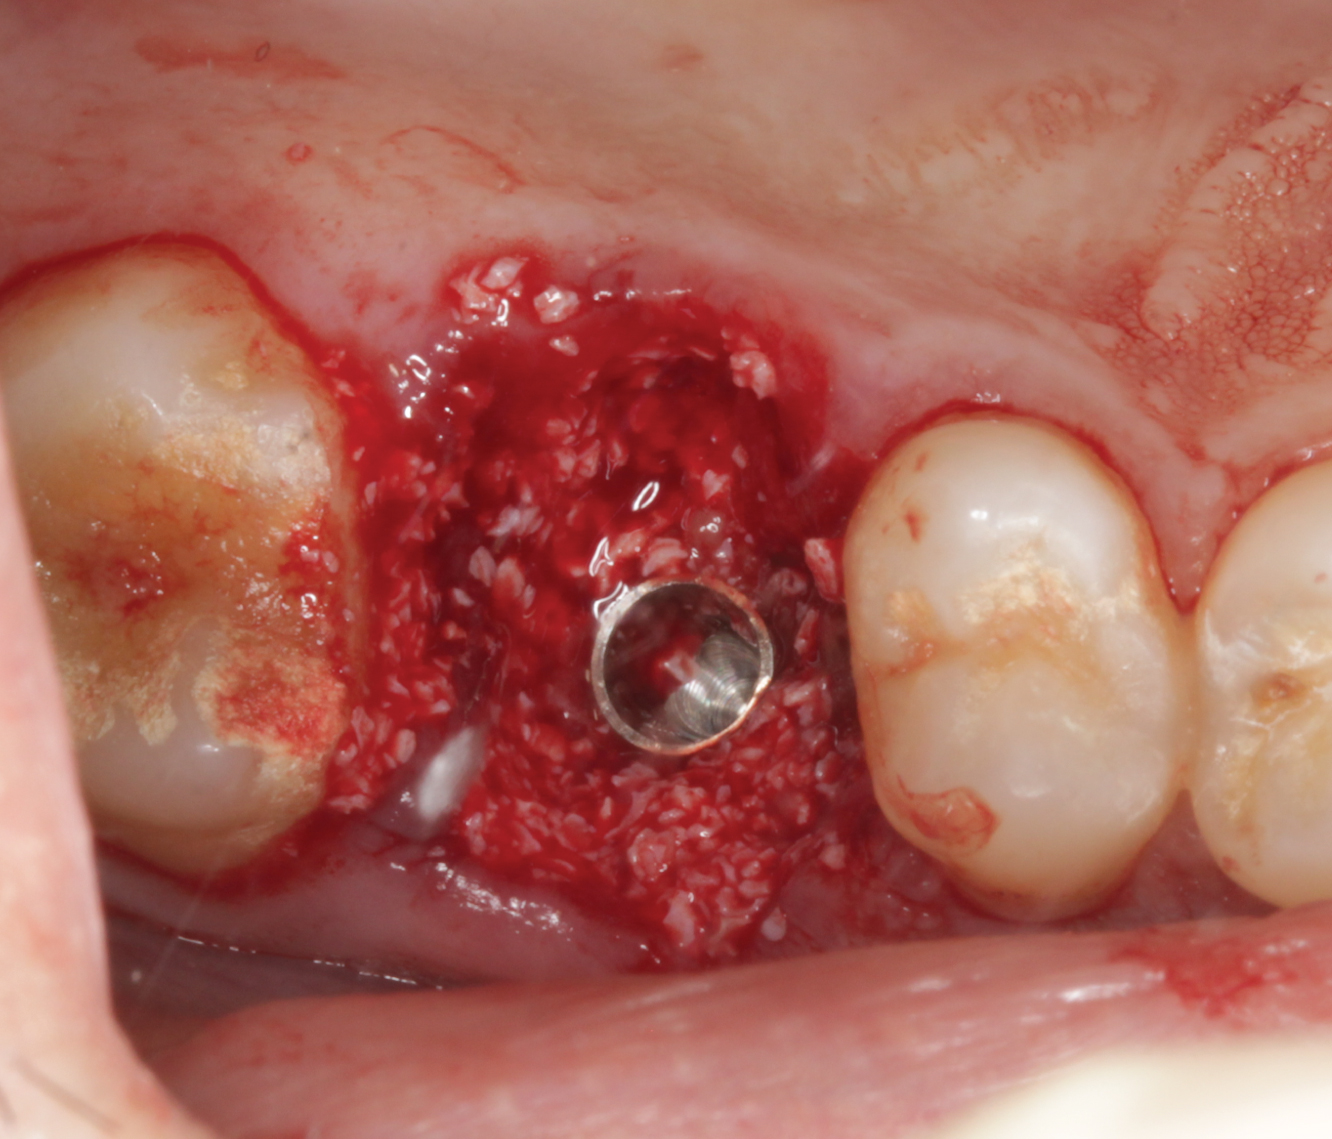

Director’s Clinical Cases

Director’s Clinical Cases